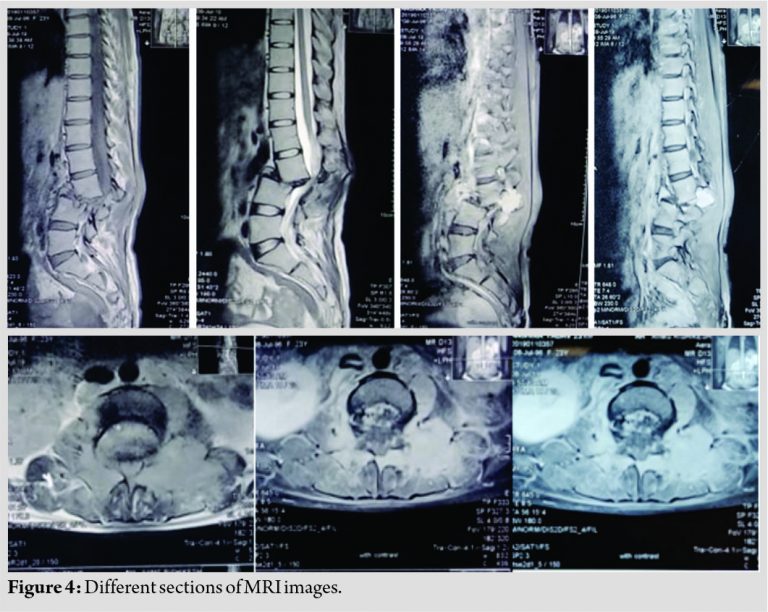

MRI revealed that a homogeneous mass was at the level of L3L4 L3L4 and on either side of the pedicles of L4 with obliteration of bilateral neural foramina. The lesion and mass were hypointense on T1- weighted images and iso to hyperintense on T2 weighted and in contrast images. There was also considerable compression on the thecal sac at the level of L3 (Fig. 4).